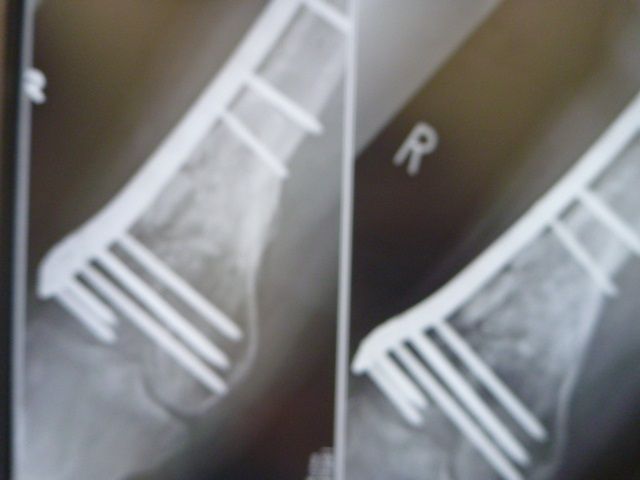

±¦¡¢È¾Ç¯Á°¤Î¥ì¥ó¥È¥²¥ó

º¸¡¢º£Æü¤Î¥ì¥ó¥È¥²¥ó

¹ü°Ü¿¢¤·¤Æ¤«¤é¡¢¤º¤Ã¤È¶õƶ¤À¤Ã¤¿Éôʬ¤¬

¤³¤³¤ËÍè¤ÆµÞ¤Ë¹ü¤¬³èÀ²½¤·¤Æ

¶õƶ¤¬Ëä¤Þ¤Ã¤Æ¤¤Æ¤¤¤Þ¤¹¡£

¶²¤é¤¯¤³¤ì¤Ï¡¢ËܳÊŪ¤Ë¥µ¡¼¥¥Ã¥È¤Ç

¥¹¥Ý¡¼¥ÄÁö¹Ô¤ò¤·¤¿°Ù¤À¤í¤¦¤È»×¤Ã¤Æ¤Þ¤¹¡£